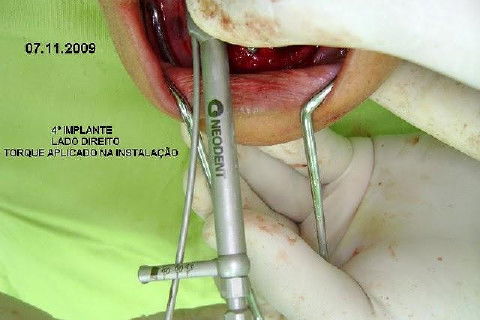

Protocolo Inferior com 5 Implantes - Parte I - Planejamento + Cirurgia

Apesar da boa adaptação e estética satisfatória, a principal queixa da paciente era a instabilidade da prótese inferior, como sempre ocorre nestes casos...atrofia do rebordo alveolar e perda da função mastigatória.